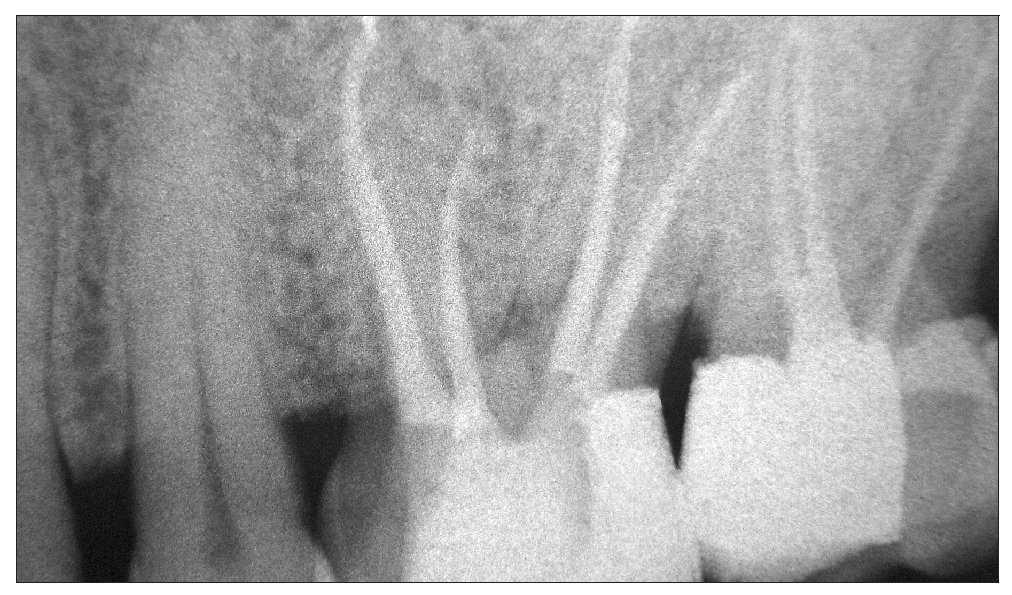

Figura 1a. Variante anatómica inusual de un molar superior en un paciente de origen asiático.

Figura 1b. El microscopio dental permitió detectar como causa de la pulpitis irreversible la apertura iatrogénica de la cámara pulpar (flecha) a nivel del conducto distopalatino y proceder a su cierre. La suposición de que el microscopio mejora los resultados del tratamiento endodóntico no está basada en la evidencia.